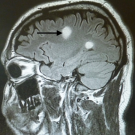

A 20-year-old man presented with double vision and tingling/electric shock-like sensations of the right side of the body.